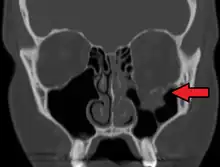

Le diagnostic est fait sur le scanner facial.

Fracture de type blow-out

L'ouverture du plancher de l'orbite est large et comminutive. En l'absence de fracture de la margelle infra-orbitaire, le blow-out est dit pur. Sinon, il s'agit d'un blow-out impur.

Le risque d'incarcération du muscle droit inférieur est faible. L'énophtalmie, par diminution du volume orbitaire, est classique.